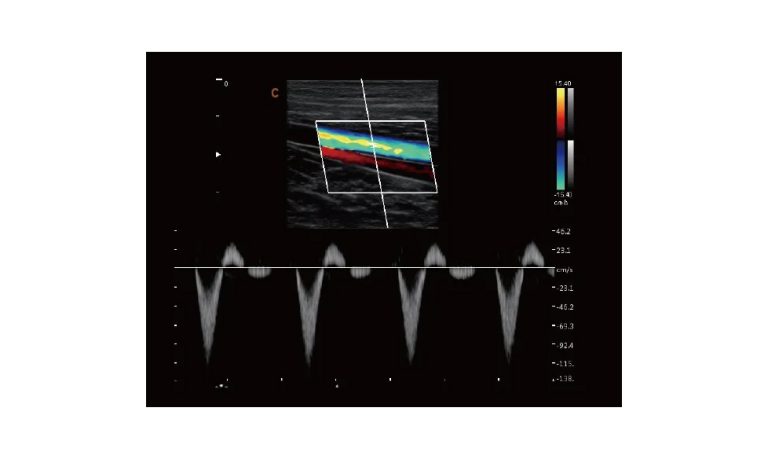

Ultrasound

Wide range of Ultrasound machines that suites a variety of applications from abdominal to rectal scans, we take in consideration how the world is moving towards mobility and mobile applications.

EBIT50/60 VET

All the power you need

The EBit provides all the power you need for today´s challenging clinical environment, yet remain ultra-portable, ultra-affordable. With its cutting-edge imaging technologies, precise and intuitive workflow, ergonomic and eco-friendly design, versatile transducers for all applications from top to toe, we firmly believe the EBit to be the very best portable ultrasound in its class today.